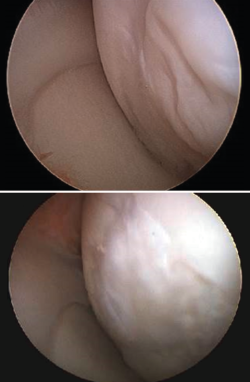

Although cartilage damage is most often of idiopathic or degenerative origin, joint cartilage injuries are also frequently caused by traumatisms (Figure 1A), i.e., joint trauma, followed by osteochondritis dissecans (OCD)(1,2)(Figure 1B).

Figure 1. Arthroscopic view of osteochondritis dissecans of the external femoral condyle.

Figure 2. Arthroscopic view of the repair tissue in two osteochondral lesions of the internal femoral condyle.

The chondral defects may be partial or complete, depending on whether the full thickness of the cartilage is affected, with involvement of the subchondral bone. In this case a repair mechanism is activated that does not produce normal cartilage but rather repair tissue lacking the biomechanical characteristics of healthy hyaline cartilage, due to a decrease in type II collagen, which is replaced by type I collagen. In addition, the chondrocytes are replaced by fibroblasts, which are unable to produce an extracellular matrix with the adequate concentration of type II collagen(3,4)(Figure 2).